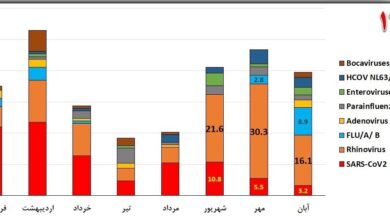

“سرماخوردگی” شایع ترین ویروس تنفسی در گردش در کشور

به گزارش خبرنگار اجتماعی سلامت جو ، با کاهش دمای هوا در فصول پاییز و زمستان شاهد افزایش بیماری های…